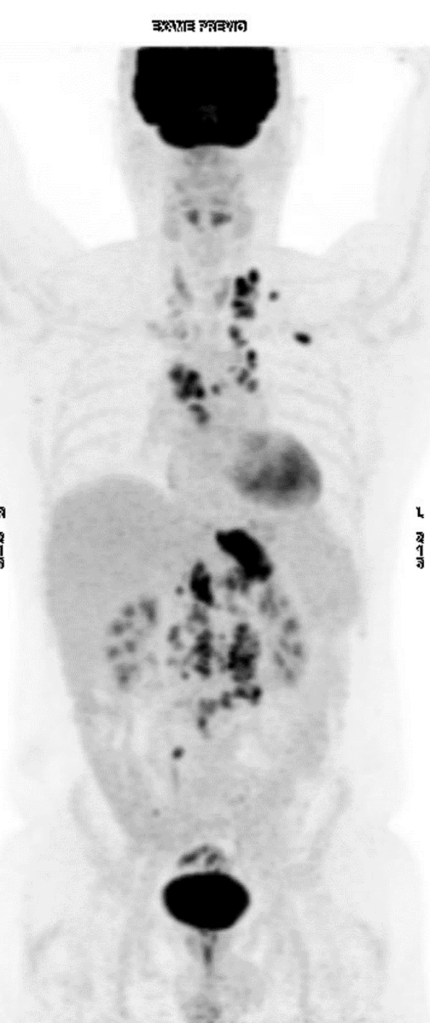

Caso clínico: Tratamento de paciente com Câncer de Esôfago avançado com PPC> 10 em 1L O caso clínico compartilhado pela dra. Marcela Crosara, traz detalhes sobre o tratamento em 1L de paciente com Câncer de Esôfago metastático CPS> 10.